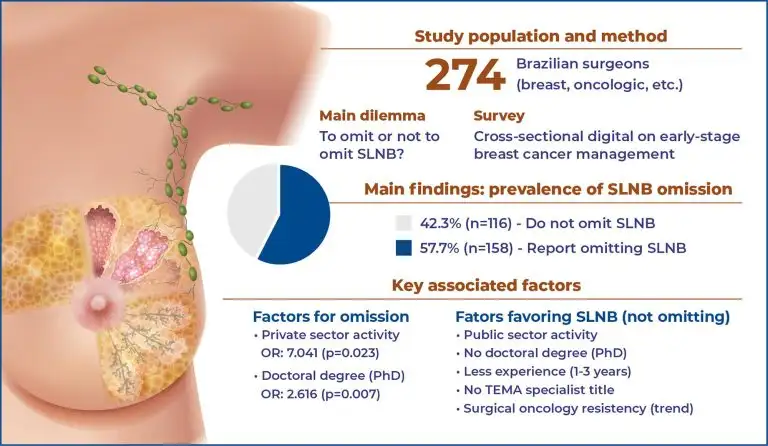

Highlights ■ De-escalation of axillary surgery has become a priority in breast cancer treatment. ■ Factors associated with the decision to omit sentinel lymph node biopsy were collected via questionnaire. ■ Sentinel lymph node biopsy was omitted more often by private doctors and those holding a doctoral degree. ■ Continuing medical education initiatives are needed to update other groups. ABSTRACT Objective: Considering the increasing number of new breast cancer cases and the morbidity associated with axillary lymph node dissection in […]